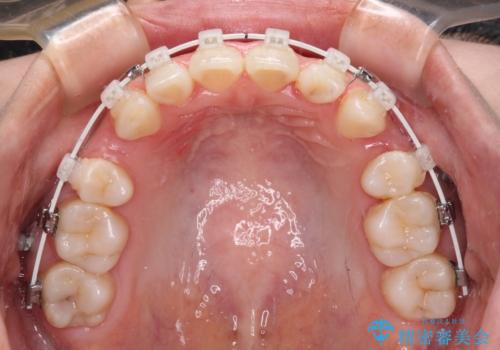

上下前歯が非接触である開咬は、インビザラインによる治療がお勧めではありますが、非抜歯矯正か抜歯矯正か悩む口元であり、途中抜歯矯正に切り替えたときに対応しやすいよう、ワイヤー装置にて治療を行うこととしました。

舌の突出癖の影響もあり、非抜歯矯正で治療開始したものの口元が突出し、唇が閉じにくくなってしまったため、途中で第一小臼歯4本を抜歯ししました。